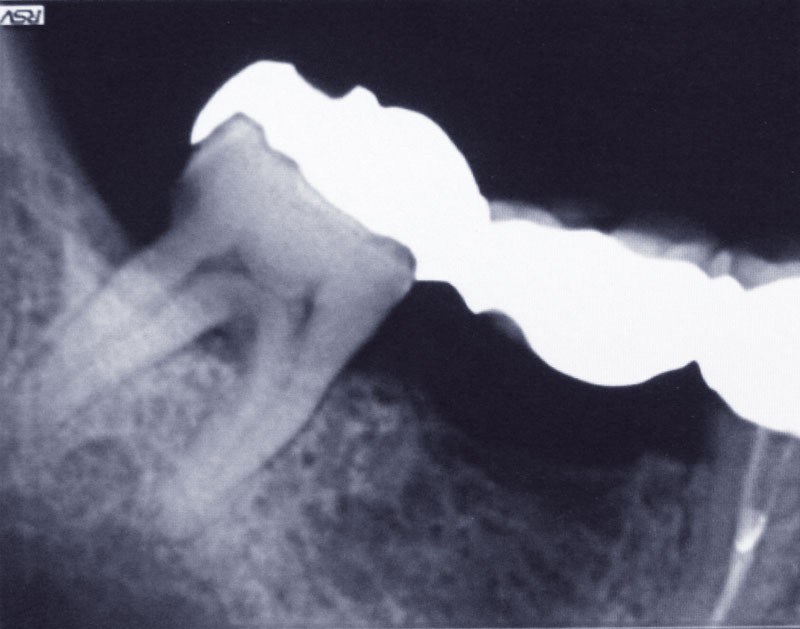

Un patient se présente pour le descellement d’un bridge 45-47 au niveau de l’onlay en 47 (fig. 1).

Afin de préserver la 45, il lui est proposé de couper le bridge en distal de 45 et en mésial de 47, de resceller l’onlay sur 47 et de poser un implant au niveau de 46, cela afin d’éviter un inévitable redescellement de la prothèse (fig. 2).

La perte osseuse vestibulaire dans ce secteur (fig. 3) ainsi…